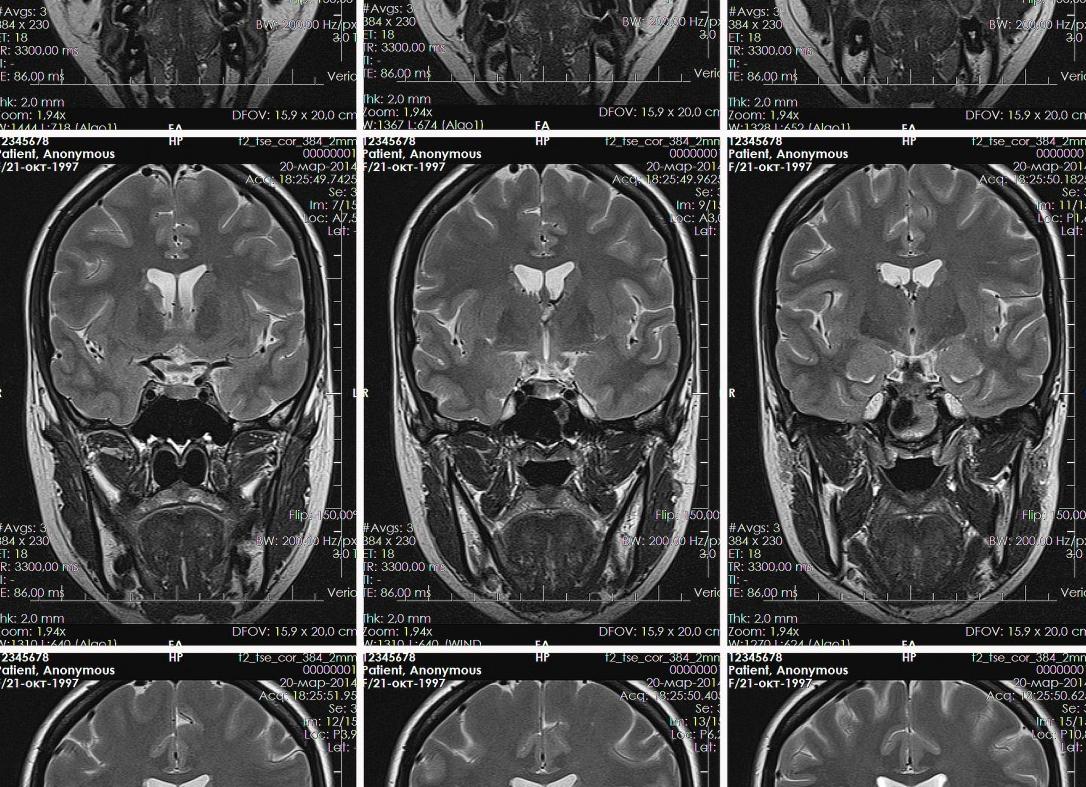

Магнитно-резонансная томография представляет собой новейшую методику диагностирования патологий. Ее используют для осмотра внутренних органов, систем и сосудов. МРТ нередко применяют при патологиях, связанных с ЛОР-органами, например, для обследования пазух носа. Обследование носовых пазух может производиться как при полноценном исследовании головы, так и отдельно. МРТ используют достаточно редко, это связано с тем, что более простые и доступные процедуры, как КТ и рентген носовых пазух, позволяют диагностировать заболевания носовых полостей достаточно точно. МРТ незаменима в сложных случаях, например, при наличии у пациента патологических процессов в области носоглотки, при осложненных клиновидных и решетчатых пазухах. Подробнее ...